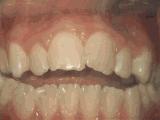

1、龅牙,前牙突出,个别牙齿扭转,通过专业评估,上下两侧各拔牙一颗后,经过矫正是变成这样的~

2、牙列不齐,牙齿异位,咬合关系紊乱,影响正常发音和正常咀嚼,经过矫正后是变成这样的~

7、牙列稀疏,个别牙齿先天缺失,导致牙列稀疏,散在间隙影响美观影响咬合,经过矫正后的是这样的~

9、牙列稀疏,个别牙齿反合,对刃咬合容易造成牙齿损伤或过度磨耗牙釉质,经过矫正后的是这样的~

10、深覆盖,咬合时,下前牙咬在上牙内侧牙肉上,容易造成牙齿和牙肉损伤,咬合功能差,经过矫正后的牙齿是这样的~

看完上面动图,是不是觉得很直观?看了这些图想要矫正的朋友是不是就安心了?当然,由于每个人的具体情况不同,所以还是要听从专业的正畸医生的建议